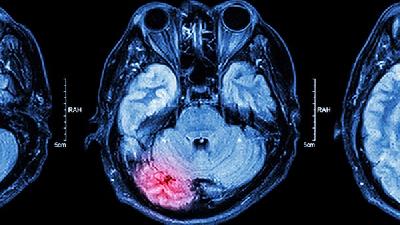

不同病因导致的脑膜炎有许多相同的症状,但是也有一些差别,比如都可以出现发烧、头痛、精神状态的改变,都可以出现脑膜刺激症、体检的时候会发现患者弯曲颈部的时候下巴不能碰到胸部。但是各个不同病因的脑膜炎,在症状上也有一些细微的差别。一般细菌性脑膜炎的病情要重一些,危及生命的可能性更大一些。而病毒性脑膜炎,相对要轻一些,不太严重,也不需要抗生素治疗。结核性脑膜炎一般表现为亚急性的病程。真菌性脑膜炎一般出现于免疫功能受损的患者。但是实际上鉴别脑膜炎的具体病因,是很困难的,往往需要对脑脊液做精细的化验分析,再加上分子生物学和病原学的检查,才有可能鉴别出脑膜炎不同的病因。